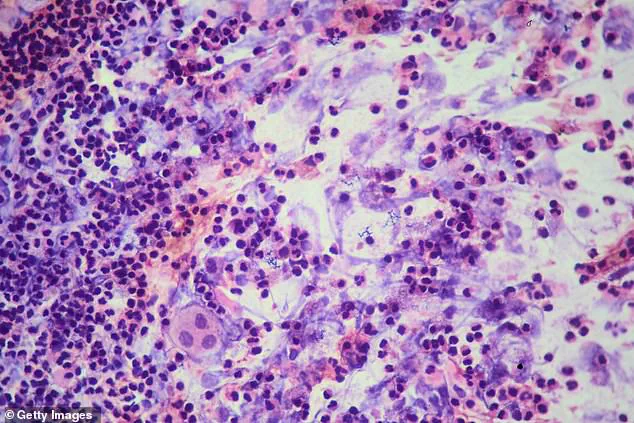

It can take up to 10 weeks to test positive for the disease because it needs to incubate first. (Pictured: Up-close molecule of TB under a microscope) It can take up to 10 weeks to test positive for the disease because it needs to incubate first, which explains why the school recently tested after November's case came to light.